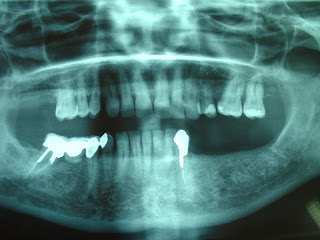

Veremos un caso de reemplazo de un sector ínfero posterior mediante implantes dentales de carga inmediata. Se han usado cuatro implantes dentales monoblock de la casa Trinon, de 3,5 mm de diámetro y 12 mm de largo, de cuello corto. una vez colocados los implantes, se toman las impresiones y los registros de mordida. se coloca un provisional fijo en la misma visita, y al cabo de quince días se carga un puente de metal cerámica de forma definitiva.